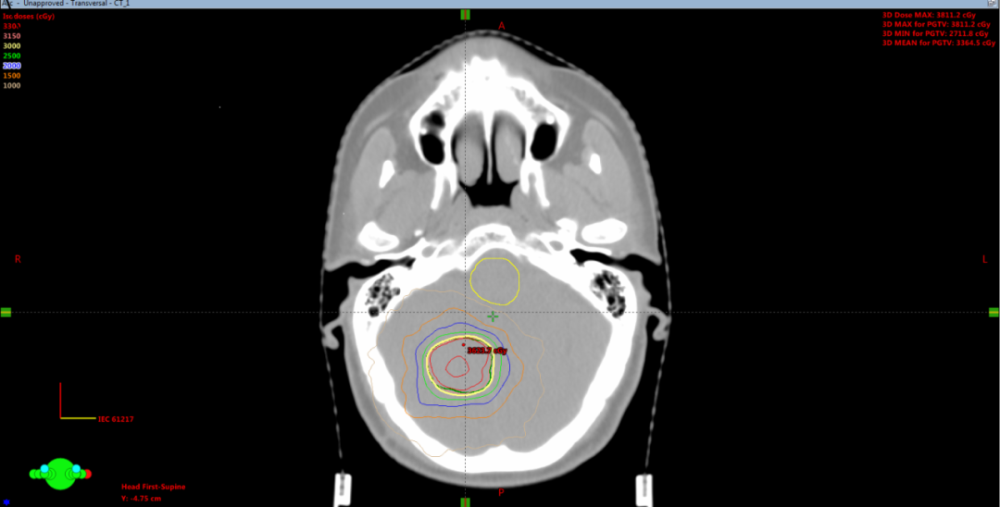

图1:患者剂量分布图(黄色曲线为处方剂量)

患者万女士(化名)于3月在我院神经外科二病区行颅内占位切除术,术后病理示:(颅内占位)中分化腺癌,诊断为结肠癌脑转移。王纪全教授在充分了解患者病情及诊疗意愿后,为提高局控率及预后,为其制定头部立体定向放射治疗方案,经过精细的放疗定位、靶区勾画、计划设计及验证,顺利完成治疗。

立体定向放疗是一种高精度的放疗技术,对人员及设备有很高要求,具有定位准确、剂量集中、损伤相对较小等优点,能够很好的保护周围正常组织,控制肿瘤进展,缓解神经系统症状,且对神经认知功能影响较小,已逐渐成为脑转移瘤的重要治疗手段,该技术的成功开展,标志我院肿瘤精准化诊疗迈上一个新的台阶。